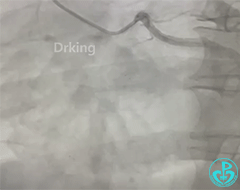

AL1,微导管辅助下XTA、P200导丝无法前行,感觉近段纤维帽坚硬。

导丝怎么扩收藏:器械难以通过的CTO病变之技术图谱_https://www.jmylbn.com_新闻资讯_第9张